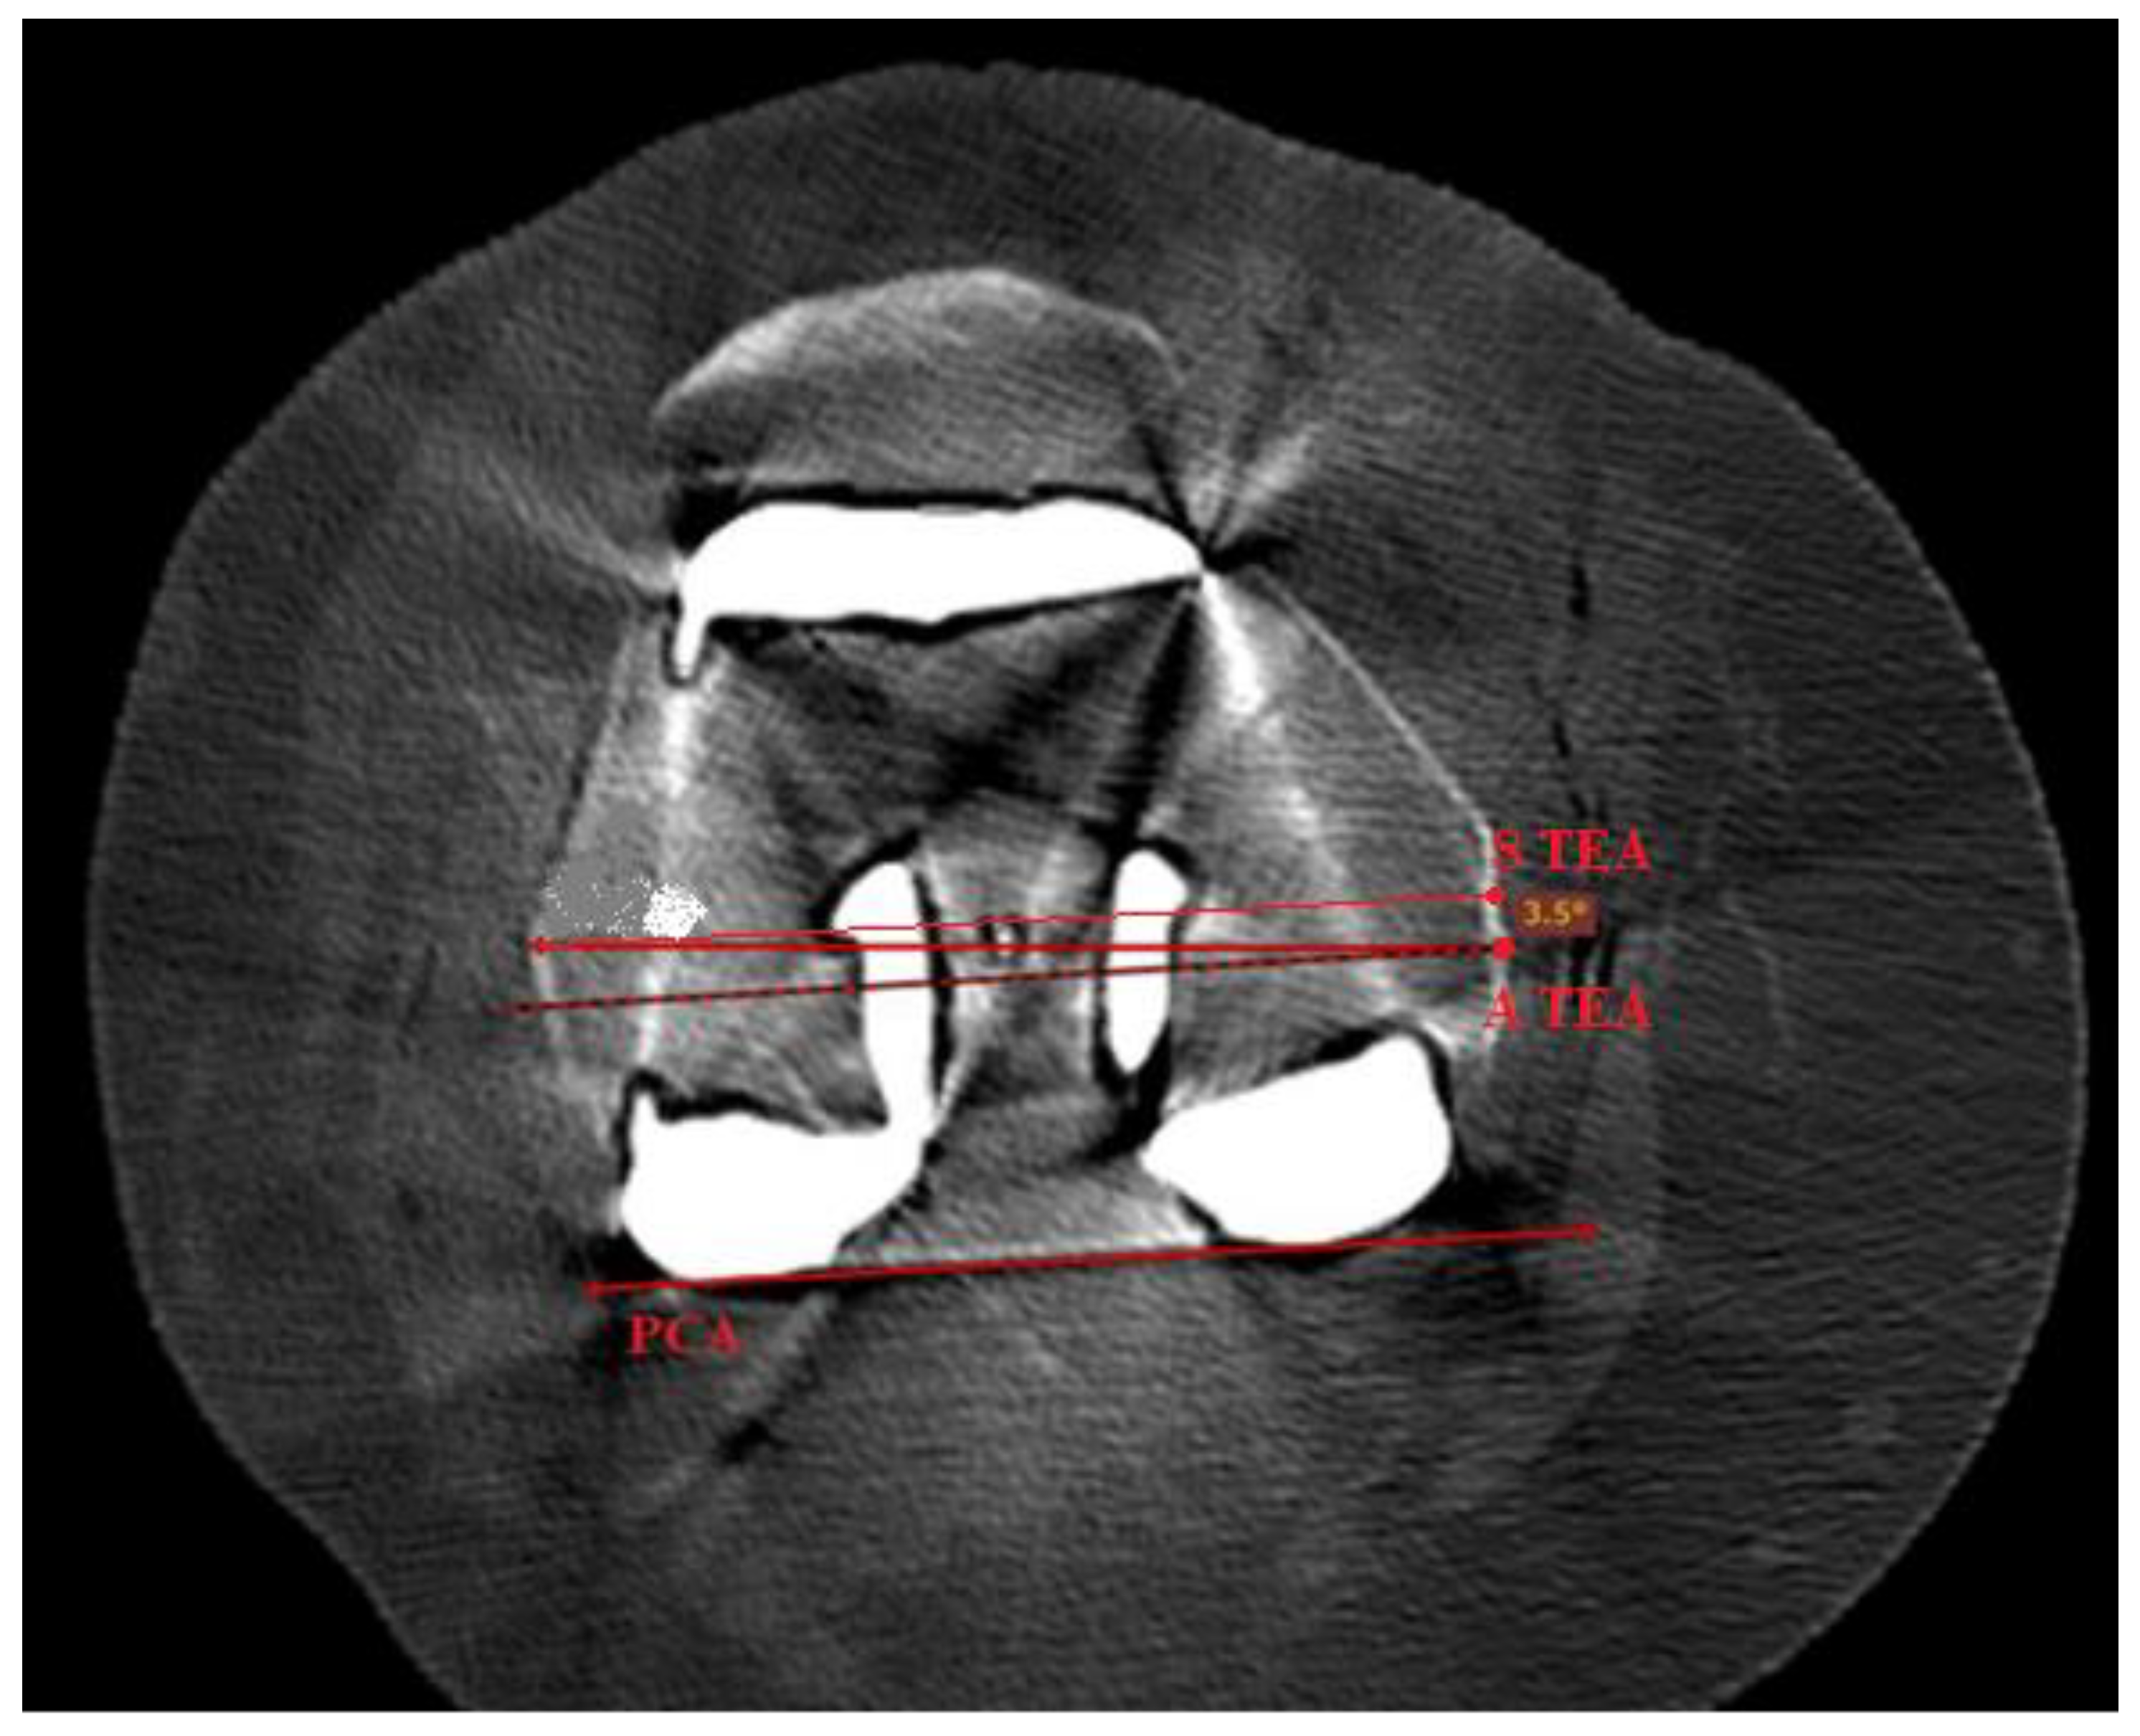

3.3. Radiographic Evaluation of Femoral Component Rotational Alignment Postoperatively

| Femoral Component Rotational Alignment | Postoperative results | 1.48 ± 1.117 | 1.33 ± 1.012 | 3.15 ± 1.2163 | 0.0013 |

| Femoral component rotational alignment | - | 1.48 ± 1.117 | 0.0006 | |

| Femoral component rotational alignment | - | 1.33 ± 1.012 | 0.0127 | |

| Femoral component rotational alignment | - | 3.15 ± 1.2163 | 0.0048 |